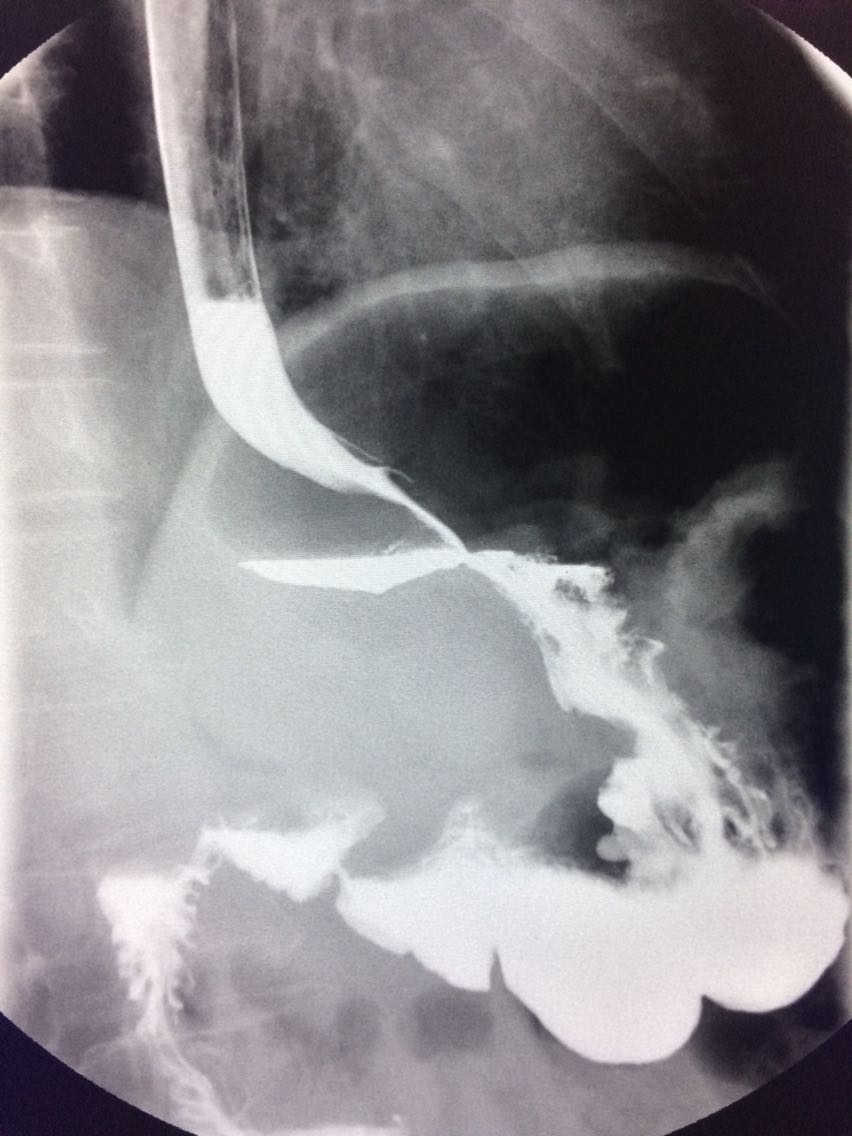

一例溃疡型胃癌。

男,45岁 反复胃疼5年余。 5年来,反复出现胃疼,进食后半小时加重,经常感觉饥饿,当地按胃溃疡,给予阿莫西林,奥美拉唑治疗,具体不详,效果欠佳,遂入院,入院来,饮食睡眠,二便可。 既往体健。 入院上消化道造影如图。

如图

讨论,诊断及鉴别诊断? 胃溃疡的影像表现? 溃疡良恶性的鉴别? 入院后行胃大部切除术。 诊断,胃腺癌。